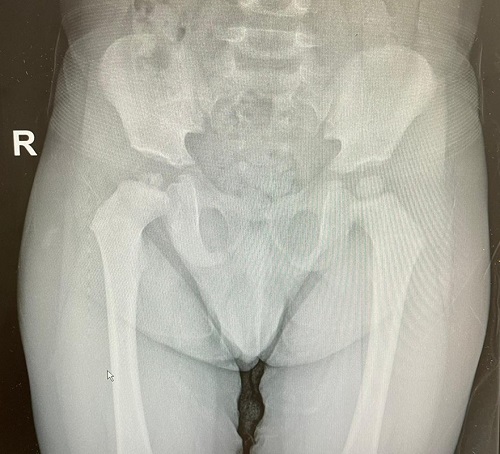

El paciente acude a los 15 días refiriendo mejoría pero persistencia del dolor tras realización de movimientos de rotación de cadera. En la exploración física se objetiva limitación a la abducción y a la rotación interna de cadera derecha, por lo que se solicita radiografía de caderas, donde se observa fragmentación de la cabeza femoral derecha. Posteriormente se realiza ecografía (Fig. 1), donde se observa un aumento de líquido intraarticular en dicha articulación, compatible con sinovitis.

| Figura 1. Radiografía anteroposterior de caderas donde se observa fragmentación de la cabeza femoral derecha |

En la radiografía realizada en la siguiente visita no se observan cambios con respecto a la previa, por lo que se plantea el diagnóstico diferencial con la displasia de Meyer y se cita en unos meses para realización de una nueva radiografía de control para ver evolución.

La displasia de Meyer es una entidad diagnosticada de manera casual en la mayoría de los casos. Se caracteriza por la fragmentación de la cabeza femoral y la existencia de efectos radiolúcidos en la radiografía. En cuanto a la clínica, los niños pequeños, como el de nuestro caso, pueden presentar cojera o molestias inguinales.

Puesto que las imágenes radiográficas son similares a las visualizadas en la enfermedad de Perthes, es muy importante realizar un correcto diagnóstico diferencial ya que el pronóstico es diferente. La displasia de Meyer no precisa tratamiento más allá del sintomático y, además, no presenta secuelas.